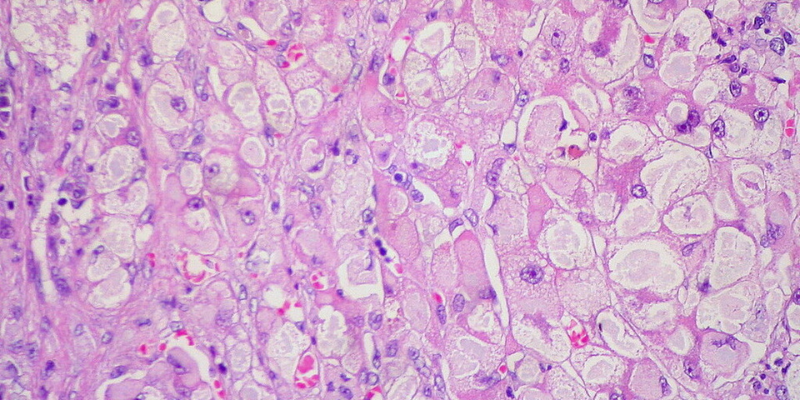

Researchers used CRISPR and mini tumours to discover more about how cancer develops and responds to the body’s immune response.

A new library documenting hundreds of mutations can help to explain why some cancers don’t respond to immunotherapies, and highlights potential pathways that could be drug targets in the future.

The researchers, from the Wellcome Sanger Institute, Open Targets, and collaborators, used CRISPR gene editing technology and mini tumours...